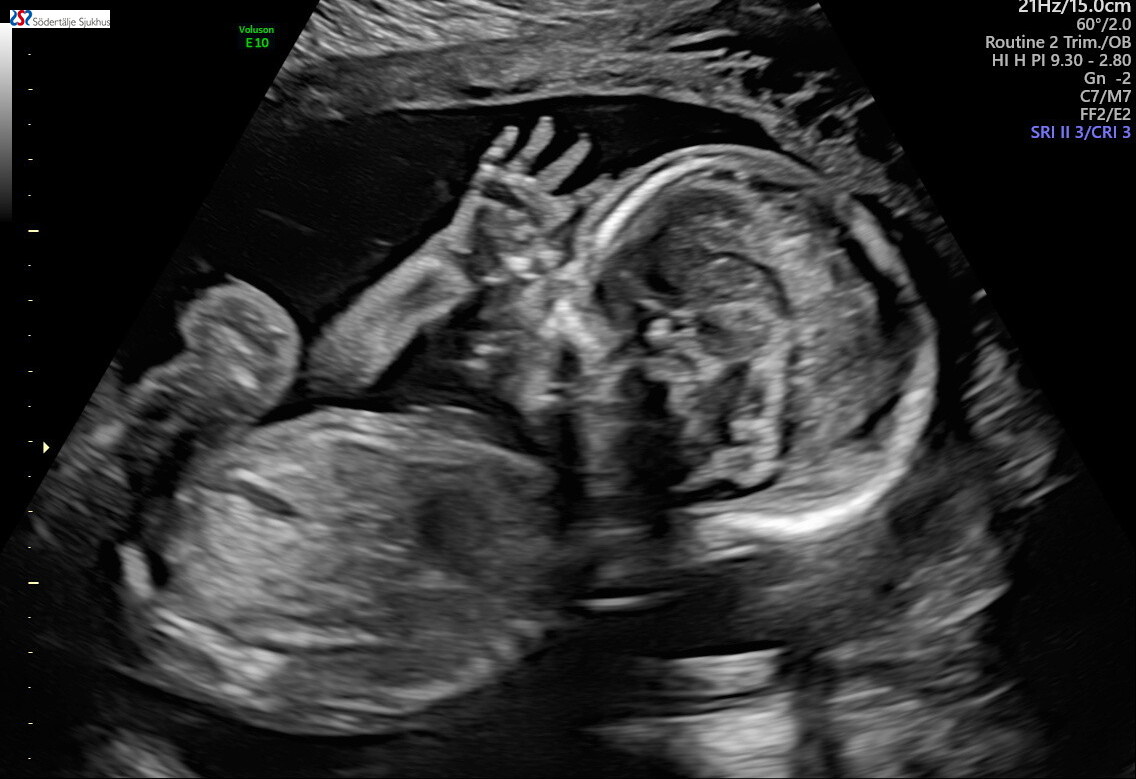

Du kom som en blixt, plötslig och oväntad, med så mycket mer kärlek än vad vi någonsin trott! Pirriga och förväntansfulla förstagångsföräldrar för att få se våran lilla bebis på ultraljud. Rutinultraljudet. Vi vill veta allt om våran lilla guldklimp. Vi resonerar att vi vill få reda på könet vid ett senare tillfälle så vi kommer få det skrivet på en lapp med oss hem.

Barnmorskan går igenom alla bebisens kroppsdelar och berättar tydligt vad som visas på skärmen. Allt ser fint ut men hon vill gå tillbaka till hjärtat och tystnar och kollar koncentrerat på skärmen. Hon förtydligar (för att lugna oss) att hennes tystnad inte behöver oroa oss. Hon hämtar förstärkning av en annan sköterska och läkare för att ytterligare kolla på hjärtat. Vi kollar på läkaren och på varandra och oron ökar medan vi undrar vad det är som sker.

En klump i magen uppstår. Vi får veta att vi ska få en remiss till Karolinska för att få ytterligare undersökning vidare på hjärtat för att det verkar vara en avvikelse. Vi hoppades på att komma hem med ett glatt besked inför påskhelgen men allt känns bara tungt… Vi får vänta 1 vecka tills att vi får komma till en barnkardiolog på Karolinska. Tankarna som hinner gå igenom oss under den veckan är så mycket oro och om det är något som är fel? Han har en avvikelse på hjärtat.

Ett stort hål och en högerställd aortabåge som kommer kräva operation. Graviditeten blir helt annorlunda med en ständig oro över våran lilla pojke. Med regelbundna läkarbesök för att kolla så att han växer i den takt han ska. Vi får reda på att han är en liten kille men han växer enligt sin kurva.